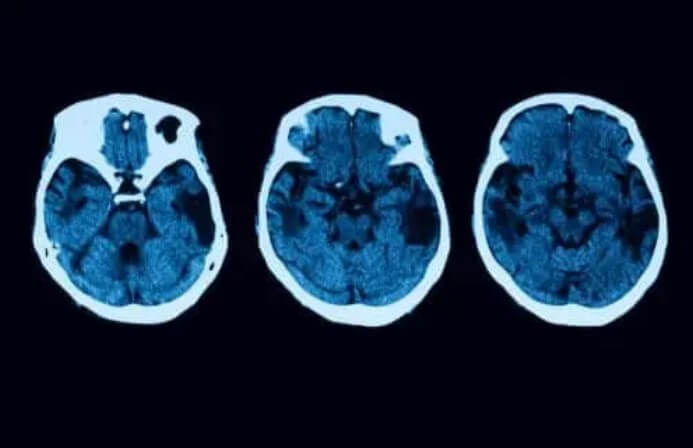

Ωστόσο, οι διαγνωστικές εξετάσεις δεν τελειώνουν εκεί. Για να ξεκαθαρίσετε οποιαδήποτε αμφιβολία, θα υπάρξουν και άλλες νευρολογικές εξετάσεις, όπως μαγνητικές τομογραφίες. Εάν όλα δείχνουν ότι μπορεί να έχετε φλοιώδη ατροφία, τότε υπάρχουν διαφορετικές θεραπείες που μπορείτε να επιλέξετε.